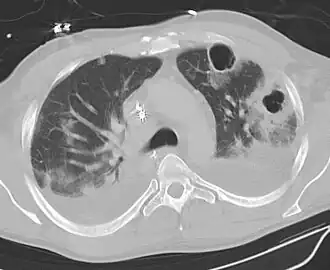

![]() Картина абсцесса лёгкого при компьютерной томографии. Видна полость в ткани лёгкого. | |

При рентгенографии лёгких выявляется в начальной стадии массивное затемнение, после прорыва абсцесса — полость с уровнем жидкости в ней. Бронхоскопия чаще всего показывает воспалительные изменения стенки бронха, связанного с абсцессом. В анализе крови — лейкоцитоз, сдвиг лейкоцитарной формулы влево, увеличение СОЭ.

До вскрытия в дренирующий бронх абсцесс лёгких проявляется лихорадкой с потом, ознобом, недомоганием, сухим кашлем, иногда болями в груди неопределённого характера. После прорыва полости в бронх появляется кашель, сопровождающийся выделением гнойной мокроты с неприятным запахом, иногда с примесью крови. До опорожнения абсцесса может определяться притупление перкуторного звука и ослабление дыхания в зоне поражения. После образования полости над ней выслушиваются звонкие крупнопузырчатые хрипы, бронхиальное дыхание с амфорическим оттенком. При перкуссии можно обнаружить звук с тимпаническим оттенком. До образования полости диагностика абсцесса лёгкого трудна. Лёгочное нагноение следует подозревать при затянувшейся пневмонии с длительным повышением температуры тела и стойким лейкоцитозом. При прорыве абсцесса в бронх рентгенологически в бывшем участке затемнения обнаруживается полость.